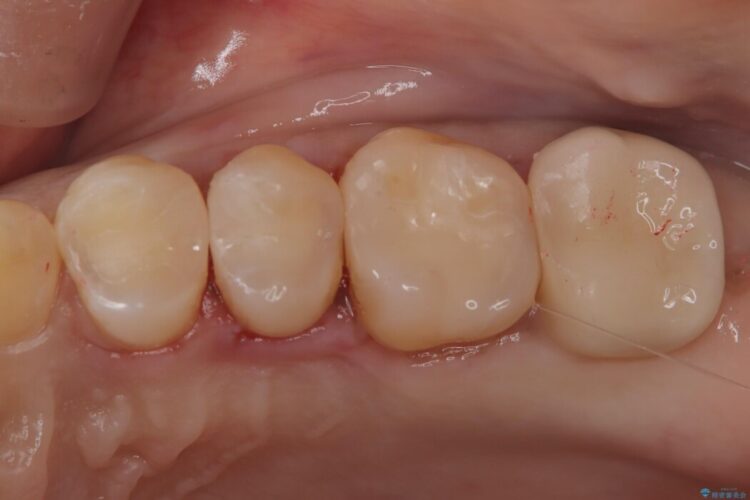

メタルインレーの下と他2歯に虫歯を認めたため治療をすることとしました。

また今後の手入れなどを考慮し、虫歯が再発しにくい素材であるセラミックを選択しました。

治療後について

セラミックは劣化しにくくつるつるとした表面に歯垢が付着しづらいため虫歯の再発を減らすことができます。